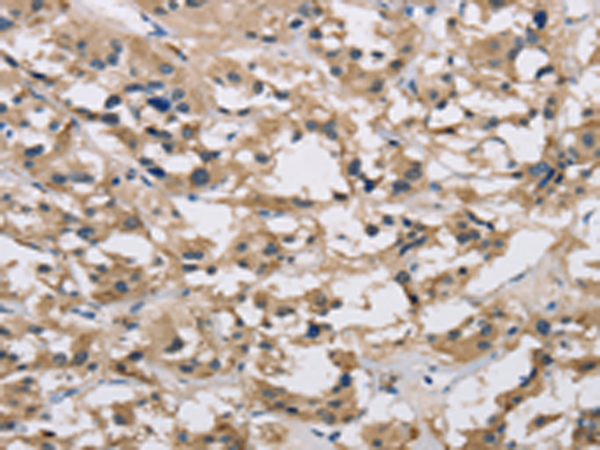

分类: 科研抗体货号: P11855别名: IMPD; RP10; IMPD1; LCA11; sWSS2608应用: WB,IHC反应种属: Human, Mouse, Rat